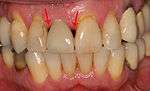

Additionally, for an implant to look esthetic, a band of full, plump gingiva is needed to fill in the space on either side of implant. The most common soft tissue complication is called a black-triangle, where the papilla (the small triangular piece of tissue between two teeth) shrinks back and leaves a triangular void between the implant and the adjacent teeth. Dentists can only expect 2–4 mm of papilla height over the underlying bone. A black triangle can be expected if the distance between where the teeth touch and bone is any greater.[18](pp81–84)